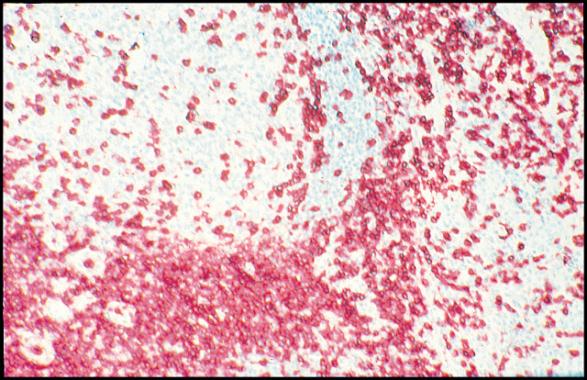

CD3 epsilon

CD3 epsilon antibody

WB, ICC/IF, IHC-Fr, FACS, IP, IHC, RIA

Human infant thymocytes and Sezary cells

Human, Pig